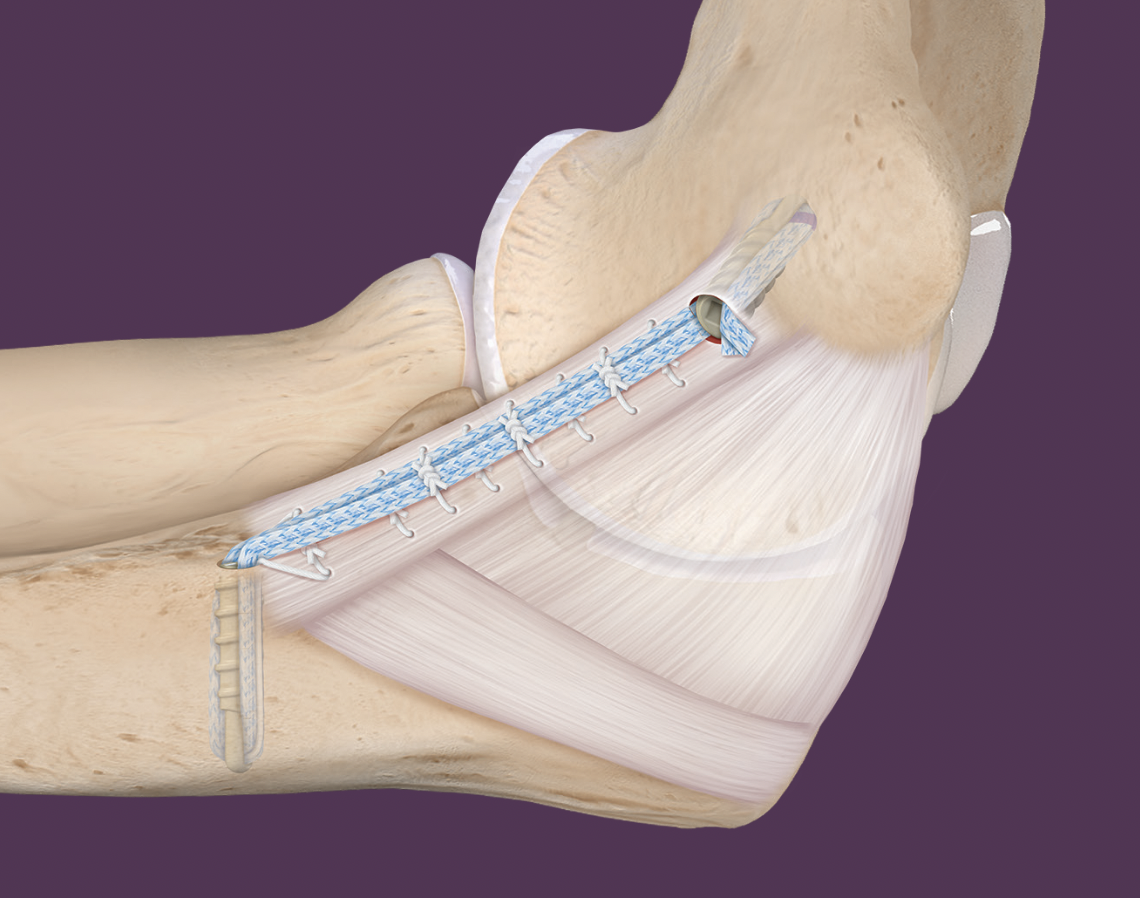

Primary UCL repair with internal brace augmentation

Technique

Arthrex internal braceArthrex internal brace

Medial incision over medial epicondyle

- protect ulna nerve

- split FCU

- expose ulna collateral ligament

- repair avulsion from medial epicondyle / sublime tubercle as indicated with anchor

- ensure isometric